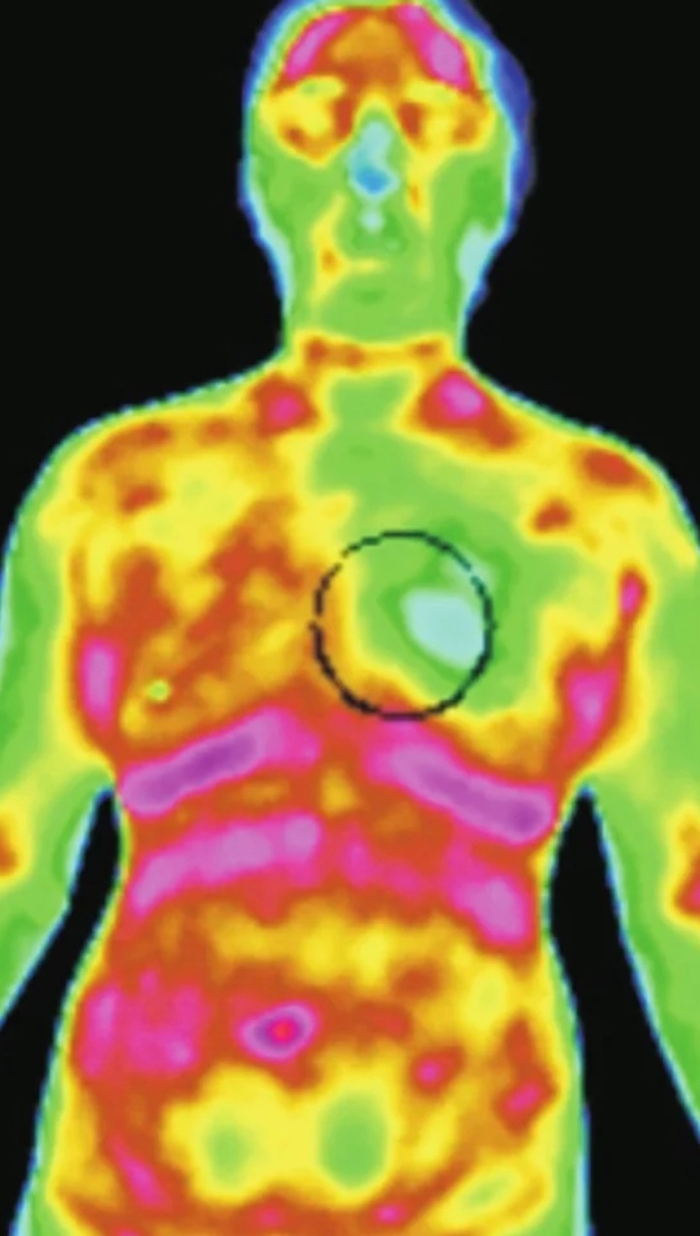

红外热成像技术最早用于中医领域,即是对人体经络腧穴的研究。红外热成像能将人体脏腑功能状态通过经络穴位热辐射变化真实的直观的记录下来,能快速准确反映经络穴位异常状态。

通常,健康人的红外热像中看不到穴位。如果红外热像中出现穴位,提示与它对应的器官出现了问题。

穴位的特点是在层析过程中出现较规则的圆形热辐射,并且深度较浅。经络是具有一定走行路径的并与脏腑功能有着特定联系的遍布全身的网络系统,在病理状态下,经络的某一段会以温度升高或降低的形式显现,提示其相关的脏腑出现问题,这种问题既可以是功能性的也可以是器质性的,比如肺脏病变,手太阴肺经可表现出异常热结构,肝胆病变,肝胆经络可表现异常热结构。